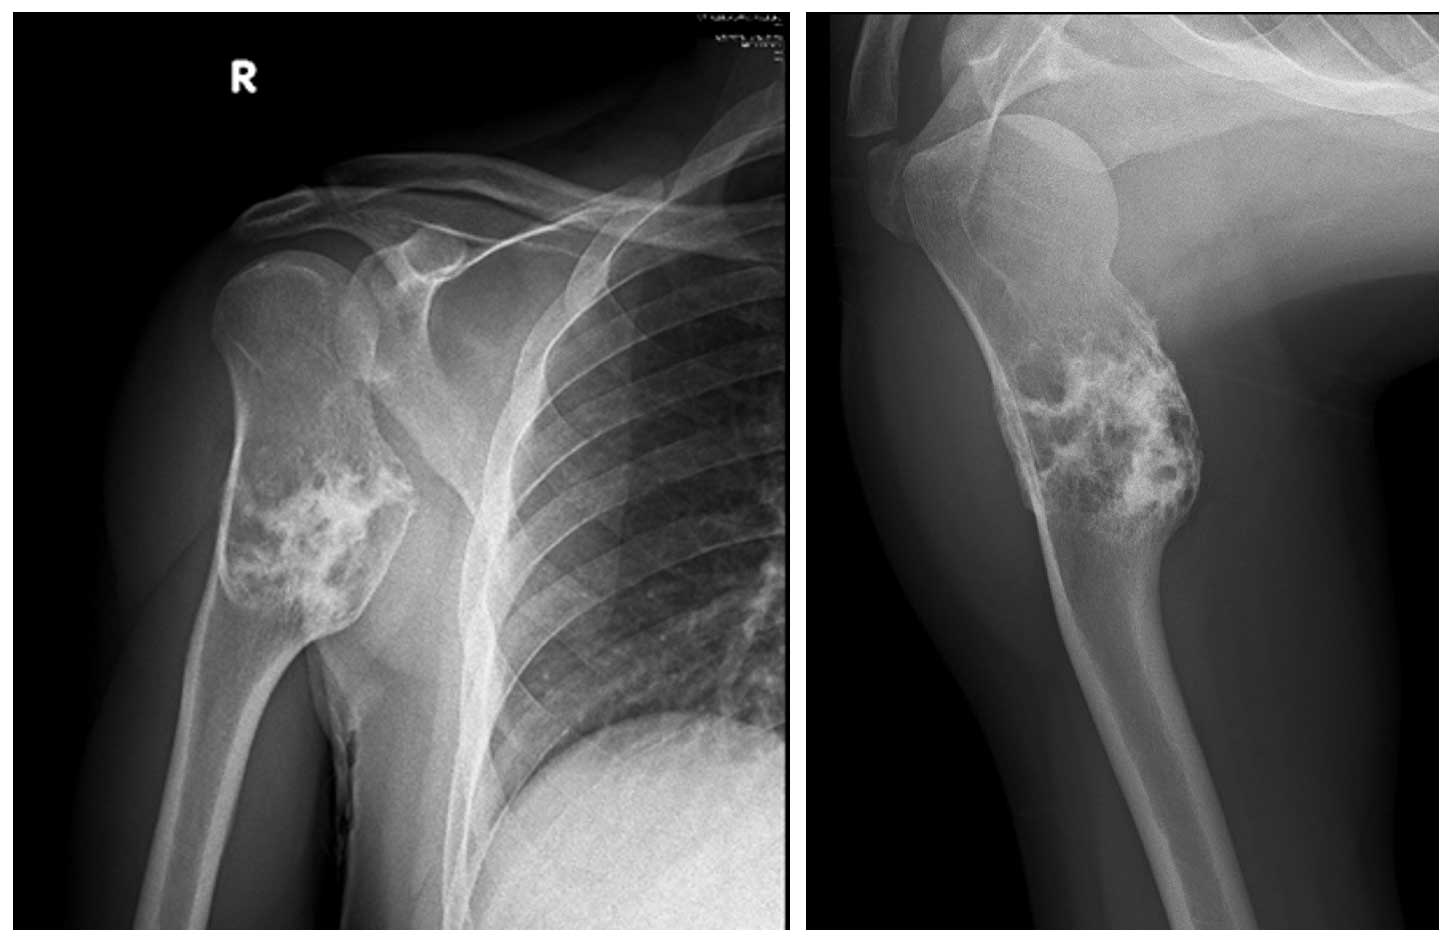

Ameliyat Öncesi: Röntgende Proksimal Humerus’ta kemikte ekspansiyona enden olan düzensiz kitle görünmekte.